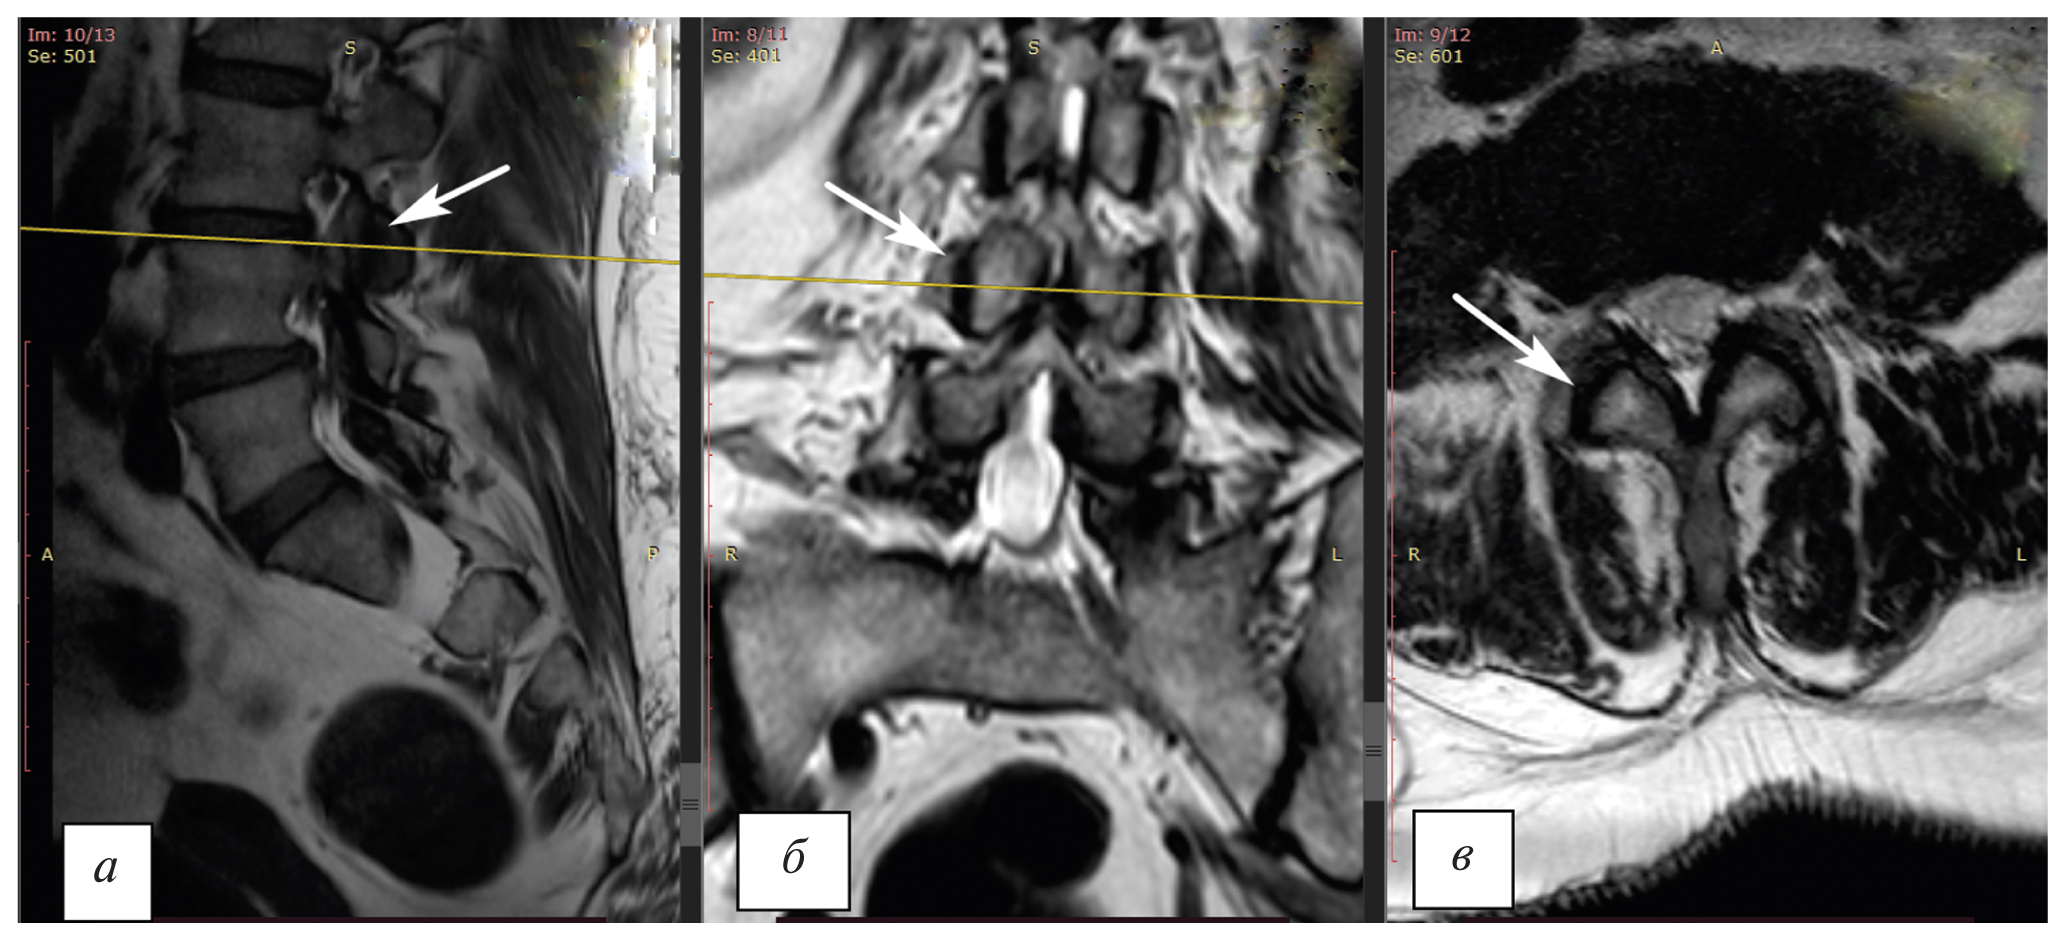

По результатам исследования поясничного отдела позвоночника методом мультиспиральной компьютерной томографии (МСКТ) выявлены дегенеративно-дистрофические изменения (рис. 2).

Рис. 2. Мультиспиральная компьютерная томография поясничного отдела позвоночника: а — аксиальная проекция; б — фронтальная проекция; в — сагитальная проекция. Стрелками указан гипертрофированный дугоотростчатый сустав LIII–LIV справа с явлением «вакуум-эффекта». / Fig. 2. Multispiral computed tomography of the lumbar spine: а — axial projection; б — frontal projection; в — sagittal projection. The arrows indicate the hypertrophied zygapophyseal LIII–LIV joint on the right with the phenomenon of the “vacuum effect”.

Диагноз: Дорсопатия. Спондилез более выраженный на уровне LIII–LIV («вакуум-эффект», люмбалгия, люмбоишиалгический и мышечно-тонический синдромы, что соответствует IV степени по классификации D. Weishaupt). Фасет-синдром. Стойкий болевой и мышечно-тонический синдром.